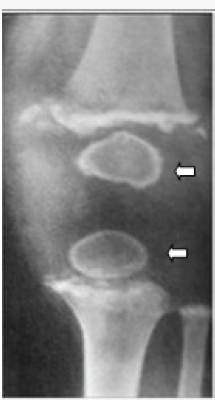

Figure 8a: Scurvy showing subperiosteal hematomas and subluxation at the knee joint.

Figure 8b: showing Wimberger's ring sign. Dense outer ring with central lucency.

Figure 8c: Scurvy- both knees showing the Frankel's lines and Pelkan spurs.

On occasion, a combination of vitamin deficiencies may be encountered, in which case both rachitic and scorbutic findings may be noted on radiographs.

Generally, conventional radiographs are enough and advanced imaging such as CT and MRI are superfluous. However, MRI may depict better pictures and show marrow changes (Figure 8).